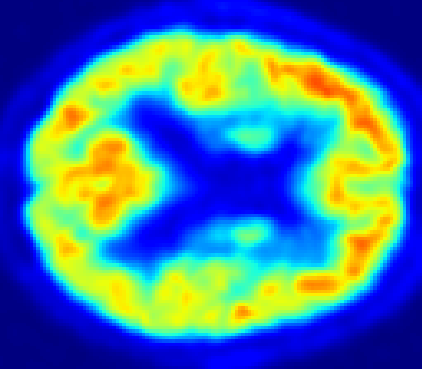

Looking at sample synthetic PET images in Fig. 3, it can be seen that all of the models are able to make reasonable predictions. The outputs of the U-PET and U-PET (no att.) look very similar and are smoothed compared to the input. The pix2pix predicts more details, which seem to be important for the discriminator. However, even though this model has finer predictions, the intensity values are worse compared to the U-PET and U-PET (no att.) as seen in Fig. 2; an example is given in Fig. 3 in the second row.

From a clinical perspective, the synthetic generated PET show a smoother version of the real PET images but keep the same pattern of FDG uptake, especially, hypometabolism in the respective brain areas. This backs up our hypothesis, that MRI contains information that correlates with the functional information of PET images. Moreover, the synthetic PET could be used as complementary visualization for physicians beyond the task of classification.

In Fig. 4, the attention maps of the U-PET are shown for multiple examples. On the one hand, the attention map of the skip connection (AttMap skip) highlights details of the brain structure, which is in agreement with the assumption that the network has to transform the specific structures of the MRI scan into the PET modality. On the other hand, the attention gates used for the classification task rather focus on more specific regions. One can observe a trend that the attention maps used for classification tend to highlight regions which have a low uptake in the PET. Since areas with a lower uptake in the PET correspond to areas with lower functional activity (hypometabolism), this focus area of the network seems reasonable with respect to the classification task.